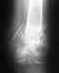

из

Добрый день! Закрытый диафизарный перелом костей голени, нижней трети. В данное время на вытяжке. Отек спал, были пузыри, заживают.Предлагается накостный остеосинтез пластиной с угловой стабильностью, 8 винтов. Возможен ли менее травматичный вариант, например аппаратом внешней фиксации, т.к сопутствующее заболевание - ОМЛ, 3 месяца после трансплантации костного мозга, повышен риск инфекционных осложнений. И, возможно ли в данный момент наложить гипс для транспортировки в другое учреждение? Перелому 9 дней. Извиняюсь за качество снимков; сделаны на 3 день.